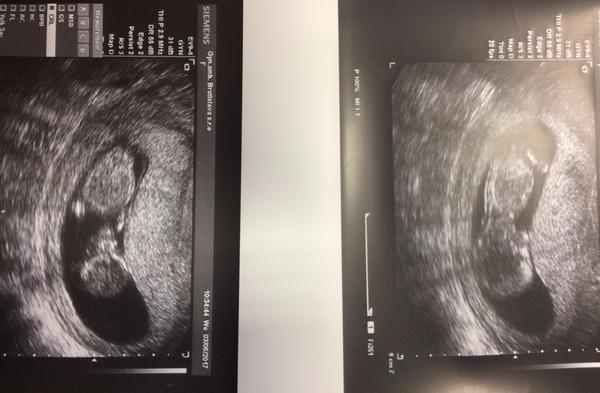

@kotatko12345 ahoj moja inak nemala by si byt teraz v 9tt? Minule si bola 7+2 čo je 8tt.nie. či od kedy sa ti ráta 9tt asi tento tyžden? A ako sa citiš čo nevolnosti?